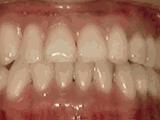

第七种:

牙列稀疏,牙槽骨过长,或者牙齿少,导致排列太宽松,零零散散,经过矫正后的是这样的~